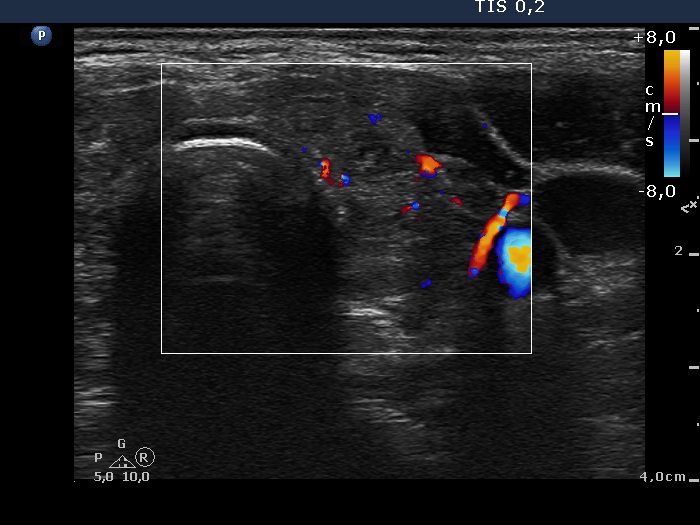

Consecutive patients with the final diagnosis of Hashimoto's thyroiditis - case 28 (481) (ultrasonographic picture 7)

Left lobe, transverse scan, color Doppler mode. The vascularization is not specific.